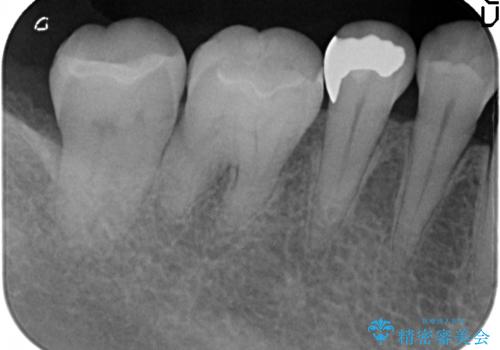

- 右下奥歯の古い銀歯をやり直したいといらっしゃった方の症例です。

銀歯を除去後、セラミックインレーにて修復しました。

- セラミックインレー…¥70,000×2費用は治療当時の料金となります

当院のセラミックインレーはemaxという強度と審美性に優れた材料を使用しています。

またプレス方式でインレーを製作しているため、削り出しで製作するCADCAMより優れた適合性も持ち合わせており、虫歯が再発しにくい修復物です。